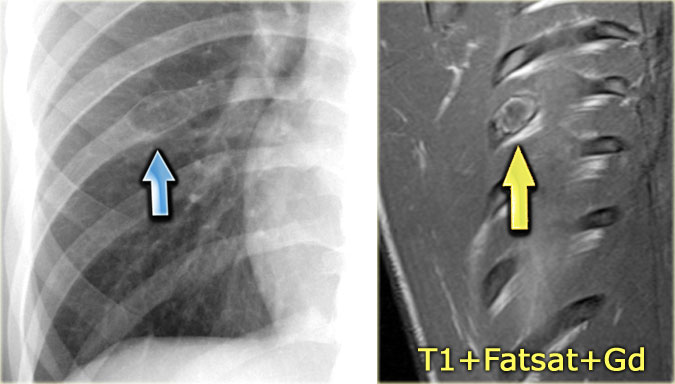

Chest X-ray shows non-specific soft tissue mass in the right lower lobe.

CT shows the mass extending from the posterior chest wall, with irregular calcifications, consistent with chondrosarcoma.

Diagnosis: high grade chondrosarcoma.